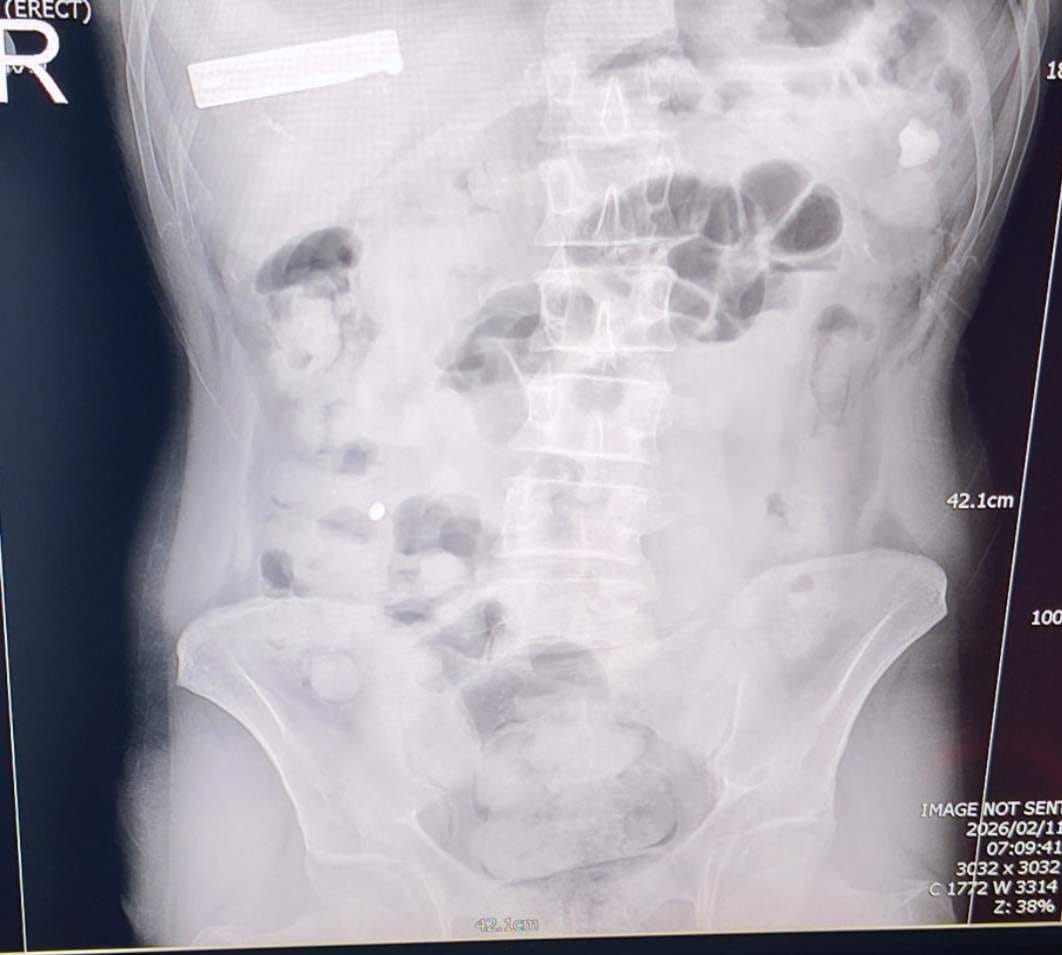

Uşak İl Emniyet Müdürlüğünce “Uyuşturucu veya Uyarıcı Madde İmal ve Ticareti” suçu kapsamında yürütülen çalışmalar ve takipler neticesinde il merkezimizde yakalanan İran uyruklu 2 şüpheli şahsın hastanede yaptırılan kontrolleri ve çekilen röntgen filmleri neticesinde mide ve bağırsaklarında çok sayıda uyuşturucu madde içeren kapsül bulunduğu tespit edildi, hastanede kontrollü bir şekilde gözetim altında tutulan şüphelilerden tıbbi müdahaleler neticesinde toplam;

93 parça halinde, 1 kilo 70 gram Metamfetamin ele geçirildi..